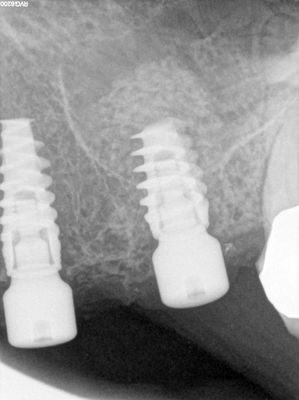

guide made for first drill, 23 atraumatic exo, implant placed 24 osteotomy too palatal, free handed implant in. 26 osteotomy prepared short of sinus floor, entry into sinus chamber with densah drills, packed about .5cc of allograft, good pushback of bone, implant placed.